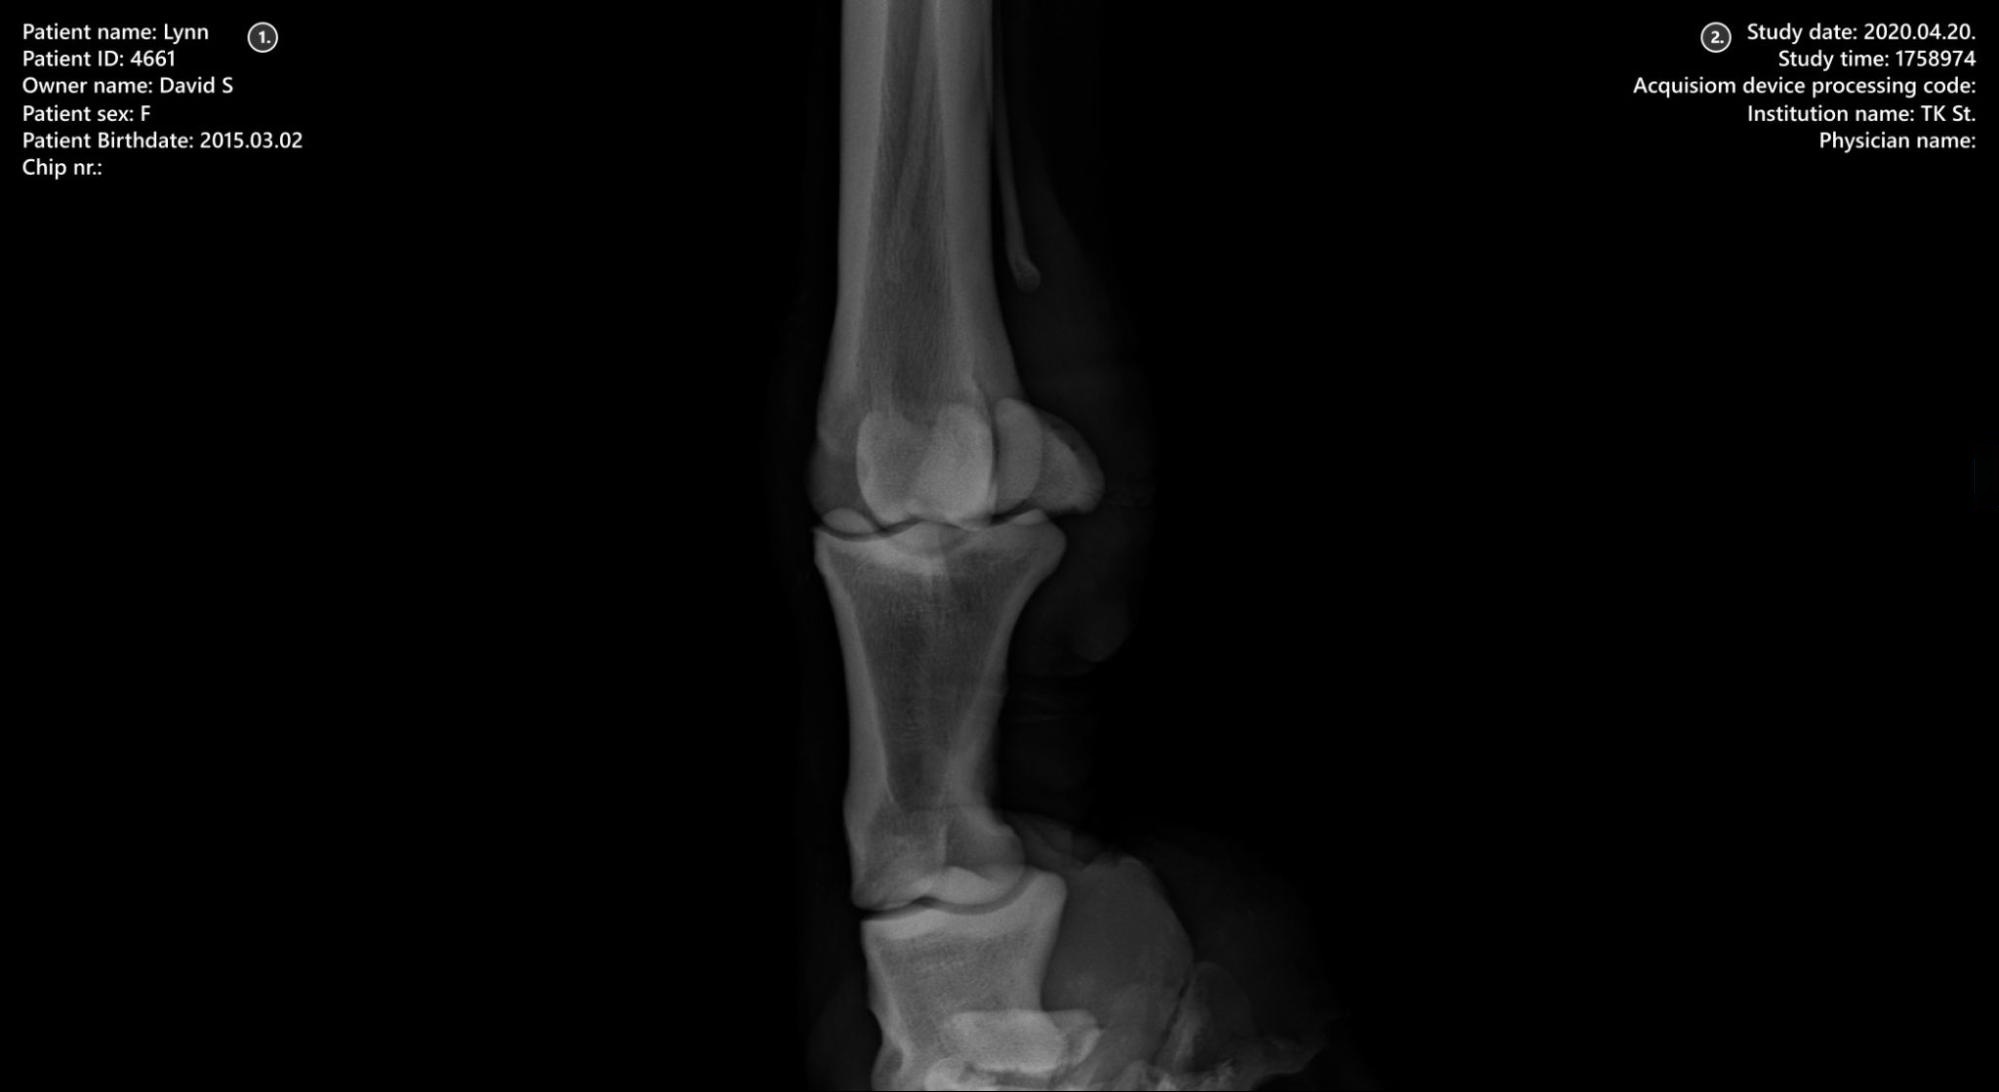

../_images/image285.jpg

1. Patient information

2. Study information